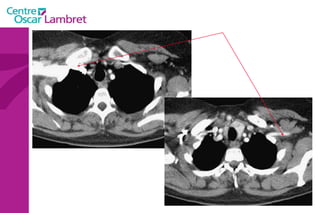

Les  3 troncs supra aortiques  naissent sur la portion horizontale de la crosse de l’aorte : Le tronc Artériel Brachio-céphalique. L’artère Carotide commune gauche. L’artère sus-clavière gauche. Tous ont une branche à destinée céphalique. L’appareil circulatoire

L’appareil circulatoire

Les Troncs Supra Aortiques s’organisent autour de la trachée à leur origine. L’appareil circulatoire

Le  Tronc artériel Brachio-céphalique  : Naît de la face supérieure du 2e segment horizontal de la crosse aortique à hauteur de T 4. Volumineux, (diamètre 12 mm - longueur 3 cm) il se dirige en haut et à droite croisant la partie droite de la trachée. Derrière l’articulation sterno-claviculaire droite il bifurque en artères sous-clavière droite et carotide primitive droite.  L’appareil circulatoire

Les  artères Carotides Communes  : La droite vient du TABC. La gauche vient de la crosse de l’aorte. Elles n’ont aucune branche collatérale. L’appareil circulatoire

L’artère carotide primitive droite : Elle naît à 3 cm en arrière de l'articulation sterno-claviculaire à la hauteur de T1. monte dans la gouttière carotidienne le long de la trachée et du corps thyroïdien, de l'oesophage puis du larynx et du pharynx.  Elle s’évase avant sa terminaison en regard du bord supérieur du cartilage thyroïde et de C4.  L’appareil circulatoire

L’artère carotide primitive gauche  : naît directement de la crosse aortique et comporte un premier segment intra thoracique en arrière du manubrium sternal. Son segment cervical est identique à celui de la carotide primitive droite.  L’appareil circulatoire